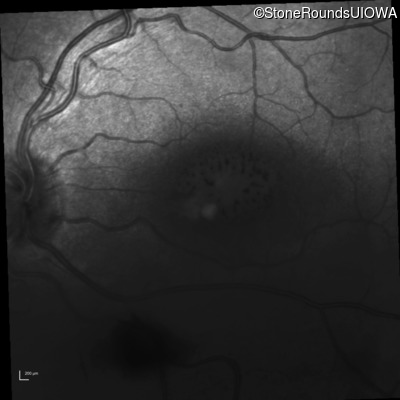

Infrared Fundus Photograph - Right - 20/70

Exemplar